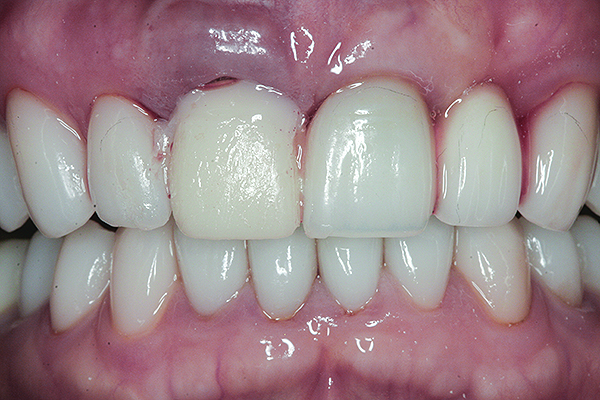

Fig 19 and Fig 20. Four-month follow-up appointment. The soft tissues had healed within normal limits (Fig 19), and the patient was pleased with the esthetic outcome of the definitive restoration (Fig 20).

Figure 19

Figure 20

The crown was inserted and secured with a luting composite (Multilink® Automix, Ivoclar Vivadent) (Figure 17); a radiograph confirmed complete removal of excess cement (Figure 18). At the 4-month follow-up appointment, the soft tissues were healed within normal limits, and the patient was pleased with the esthetic outcome of the definitive restoration (Figure 19 and Figure 20).